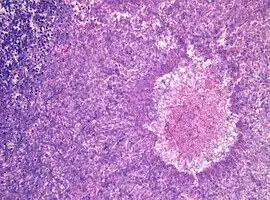

Histopathology of aspergilloma, H&E staining

Although most fungi—and especially Aspergillus—fail to grow in healthy human tissue, significant growth may occur in people whose adaptive immune system is compromised, such as those with chronic granulomatous disease, who are undergoing chemotherapy, or who have recently undergone a bone marrow transplantation. Within the lungs of such individuals, the fungal hyphae spread out as a spherical growth. With the restoration of normal defense mechanisms, neutrophils and lymphocytes are attracted to the edge of the spherical fungal growth where they lyse, releasing tissue-digesting enzymes as a normal function. A sphere of the infected lung is thus cleaved from the adjacent lung. This sphere flops around in the resulting cavity and is recognized on x-ray as a fungus ball. This process is beneficial as a potentially serious invasive fungal infection is converted into surface colonization. Although the fungus is inactivated in the process, surgeons may choose to operate to reduce the possibility of bleeding. Microscopic examination of surgically removed recently formed fungus balls clearly shows a sphere of dead lung containing fungal hyphae. Microscopic examination of older lesions reveals mummified tissue which may reveal faint residual lung or hyphal structures.[4]